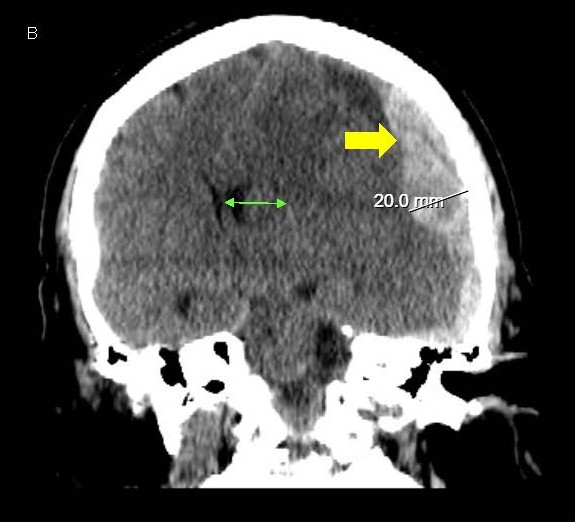

On day 4 of postoperative care, she developed right face and arm twitching along with rightward gaze deviation consistent with clinical focal onset motor seizures. VEEG showed the presence of left central onset epileptiform discharges, LPDs and multiple seizures with secondary generalization lasting 1-2 minutes each (Figures 3A and 3B). Clinically, the seizures presented with rightward gaze deviation, right jaw/mouth twitching and biting on the breathing tube and right arm twitching.

Figure 3. A, B) Screenshots from Video EEG showing LEFT hemispheric onset seizures (marked by red arrows).